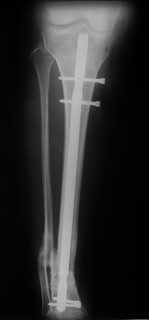

Ранее обсуждаема тема http://weborto.net/forum/1164105478/, http://weborto.net/forum/1192794837/Больная оперирована. Произвели удаление проксимальной части штифта, далее рассверлили канал до 12 мм,Подвели и одели на конец отломка устройство с определенными техническими трудностями( проводник пришлось изогнуть, упиралось при входе в заднюю стенку, что значительно усложнило его последующее вращение, несколько раз удаляли устройство, т.к. полностью утрамбовывалось костной стружкой ) совместили отверстие на втулке и штифте и заблокировали отломком винта ( винт заранее надпилили по диаметру втулки и обломали после введения). Отломок удалился без проблем.Заштифтовали 11 мм реконструктивным штифтом, увы, устранить деформацию полность даже поллер винтами нам не удалось. Интраоперационно на экране ЭОпа оан выглядела не так критически, как на контрольных снимках после операции. Задним умом надо было отложить штифтование после репозиции в аппарате (прав был А.Н.Челноков!), слишком были заняты идеей удаления отломка штифта не оценив проблему устранения деформации. В п/операционном периоде разрешили дозированную нагрузку на конечность.С надеждой на критику и обсуждениеС уважением к сообществу В. Машталов

Судя по р/снимкам у Вас всё отлично получилось, то что немножко допустимое смешение осталось это видимо помешало сросшийся малоберцовка.